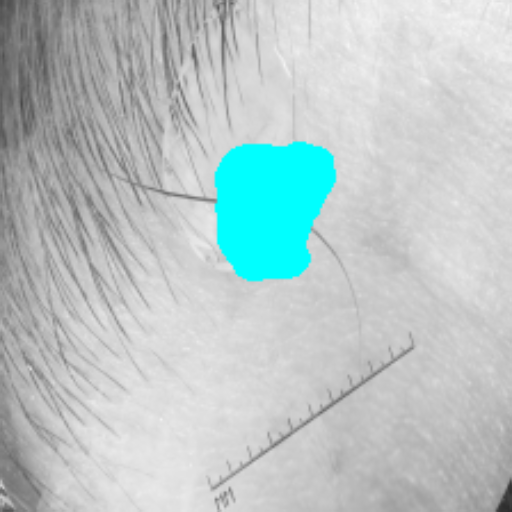

The ISIC 2017 dataset [36] contains training, validation, and test images for skin lesion segmentation. Following prior works, we report accuracy (ACC), intersection-over-union (IoU), and Dice coefficient for binary segmentation. The dataset is publicly available.333https://challenge.isic-archive.com/data/#2017

Figure 3 presents a qualitative comparison of segmentation performance on examples from the Synapse, BTCV, ACDC, and ISIC17 datasets. The first two examples (from Synapse) highlight variations in segmentation performance among U-Net, TransUnet, Mamba-Unet, and Swin-Unet. While Swin-Unet performs well in the first example, its performance decreases in the second example, particularly in segmenting the organ highlighted in blue. Additionally, it misclassifies background regions as the class highlighted in orange. In contrast, our approach demonstrates high robustness in segmenting all classes accurately and aligning well with the ground truth masks.

Across BTCV, ACDC, and ISIC17, the comparison methods exhibit varying performance depending on the task and class. For instance, Mamba-Unet struggles to segment multiple organs in BTCV, even misclassifying certain classes as others. In the ACDC dataset, both TransUnet and Mamba-Unet perform poorly in segmenting the three classes. In the last column (ISIC17), Swin-Unet oversegments the skin lesion compared to the ground truth. Unlike the comparison models, our approach consistently delivers effective segmentation across different tasks and datasets.

These qualitative findings further reinforce the quantitative results presented in the experimental section, demonstrating the effectiveness of our MambaCAFU model in handling binary and multi-class segmentation across diverse medical imaging modalities and tasks.

Slice GT Unet TransUnet Mamba-Unet Swin-UMamba MambaCAFU-V1

Figure 3: Visual comparison of segmentation examples from Synapse (first two examples), BTCV (3-4 examples), ACDC (5th example) and ISIC17 (last example). Columns: input slice, ground truth, Unet, TransUnet, Mamba-Unet, Swin-UMamba, and MambaCAFU-V1.